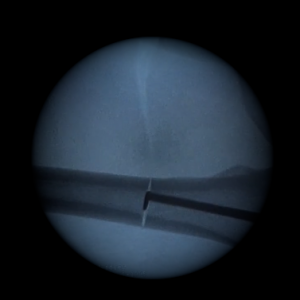

Kit de scies intramédullaires

Notre kit de scies intramédullaires facilite la réalisation d’ostéotomie grâce à la sortie progressive de la denture.